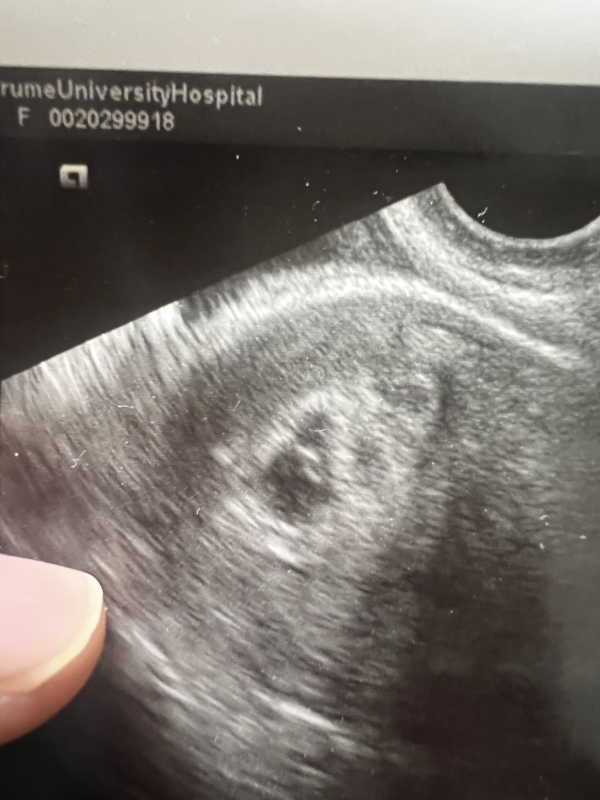

5週6日の日の真夜中に出血しだしてすぐに病院に受診しエコーしてもらってその時は赤ちゃんがいました。

真夜中に出血をしていて、受診をされた際には赤ちゃんの様子を確認することができていたのですね。

お写真を拝見いたしました。

はっきりとしたことはわからないのですが、おりものとも違うように感じました。

もしかしたら、赤ちゃんの可能性もある全く否定はできないかと思いました。